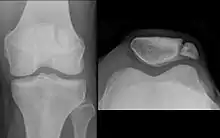

The patella can break in various ways depending on the way it is injured, and into two or more pieces.[1] Types include transverse, with one fracture line and is the most common type,[5] marginal, osteochondral and the rare vertical type, or stellate, where a direct compression force gives rise to a comminuted pattern.[5][7] Patella fractures can be further classified as displaced, where the broken ends of bone do not line up correctly and separate by more than 2mm, or undisplaced and stable where pieces of bone remain in contact with each other.[1][7] If fragments of patella bone stick out from the skin it is known as an open patella fracture, and closed if the overlying skin is intact.[1]

Transverse fracture of patella

Comminuted fracture of patella

Osteochondral fracture of patella

Vertical patella fracture